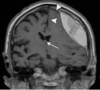

What type of herniation is depicted by the arrow? [1] Uncal Central (transtentorial) Cingulate (Subfalcine) Transcalvarial Upward cerebellar (transtentorial) Downward cerebellar (Tonsillar)

**Uncal** Central (transtentorial) Cingulate (Subfalcine) Transcalvarial Upward cerebellar (transtentorial) Downward cerebellar (Tonsillar)